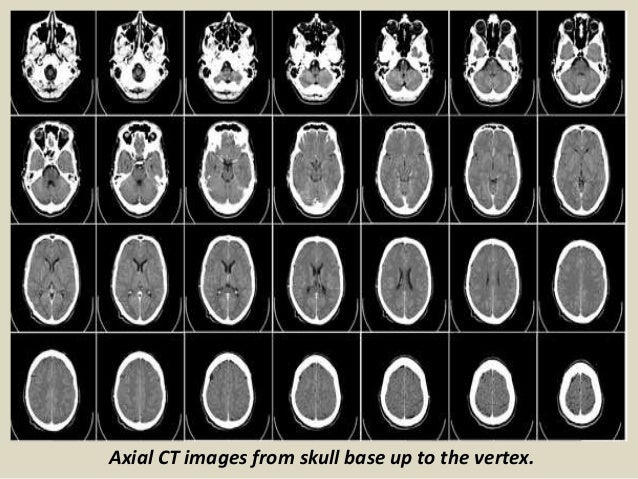

Presentation1.pptx, Radiological Anatomy Of The Brain.

Presentation1.pptx, radiological anatomy of the brain. www.slideshare.net

radiological presentation1